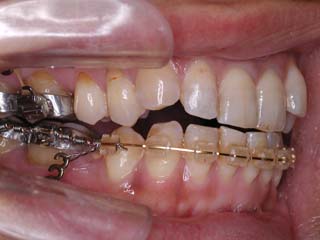

この症例では、上顎にリンガルブラケット矯正装置(Kurz)が用いられています。

この症例では、目的外使用のオーソアンカー SMAPシステム が用いられています。

本症例について検査診断の結果、開咬、叢生、下顎前突傾向を認めました。患者希望を考慮し、治療メカニクスとして、非抜歯配列、上顎のみリンガルブラケット矯正装置、下顎唇側マルチブラケット矯正装置、および、目的外使用のオーソアンカー SMAPシステムを用いることにいたしました。